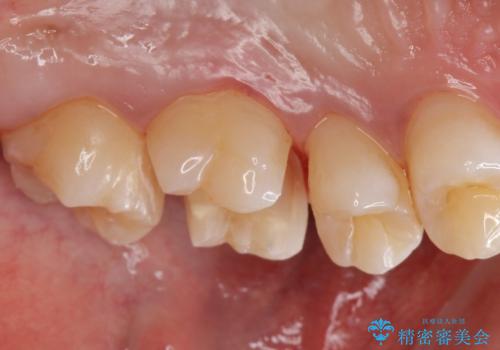

コンタクトカリエス治療。

- 歯と歯の間に虫歯(コンタクトカリエス)が見られたので拡大鏡下で取り除き、e-maxインレーで治療を行いました。